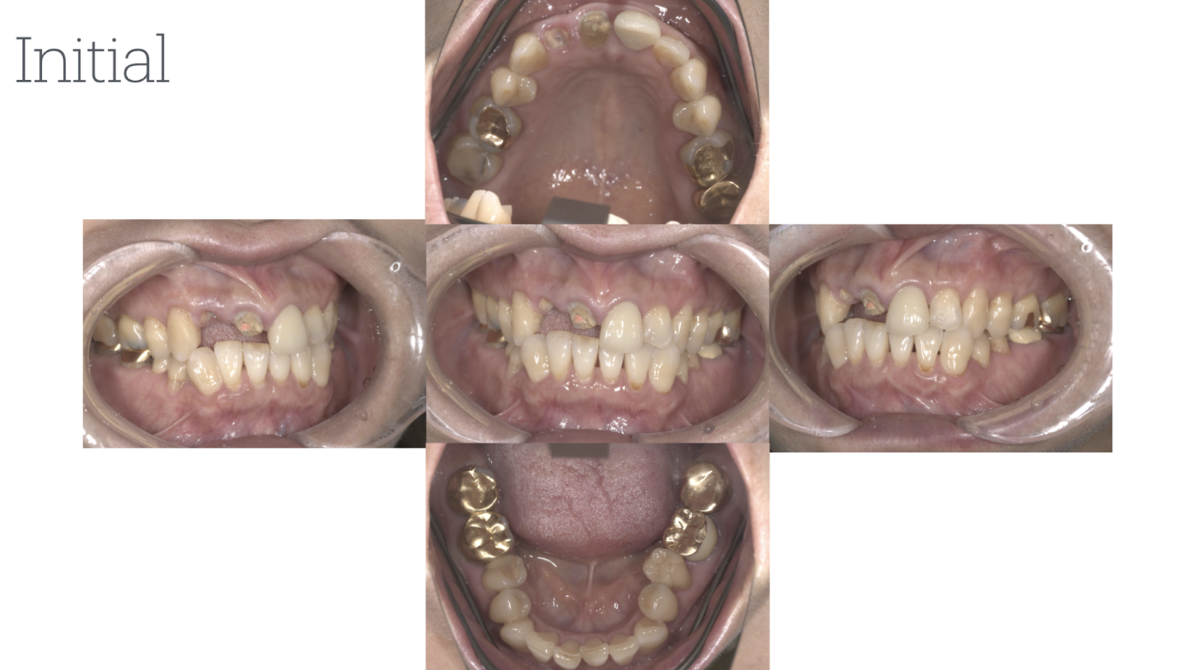

患者1

年齢性別:60代男性

主訴:定期的なメインテナンスを長年行ってきたが、前歯が揺れ始め、奥歯が噛めない状況になったため、当院にて相談。このままでは歯を失うリスクがあったため、全顎的な治療を希望。まずは、奥歯が噛めるように矯正治療を開始。同時に歯周治療を徹底的に行った。その後、保存不可能な歯は抜歯を行い、インプラント治療・被せ物による噛み合わせの調整を行った。現在、治療後定期メインテナンスを行ってい、安定した状態を保っている。